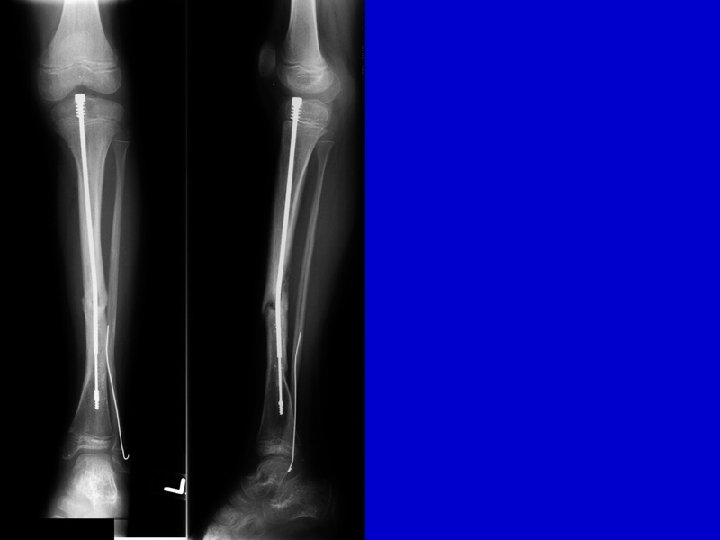

Type I Treatment Lateral AP

preop postop

Flexible IM nail 3 year follow-up